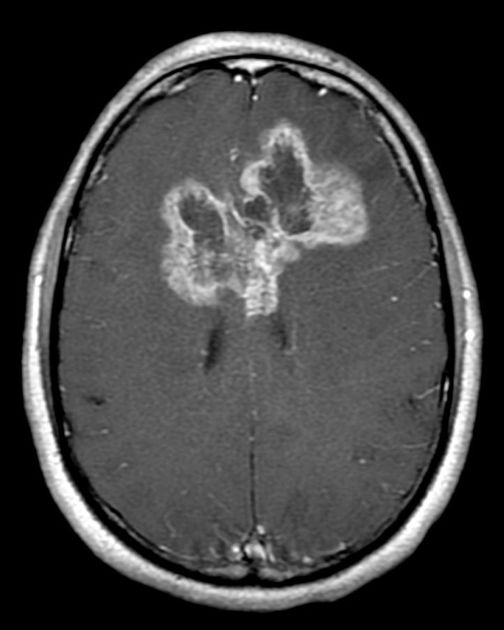

2/ T1-Weighted MRI β Anatomy & Tumor Enhancement

π₯οΈ Appearance:

β Gray matter = Dark

β White matter = Bright

β CSF = Dark

π Key Uses in Neurosurgery:

β Anatomical detail of brain structures

β Pre- & Post-contrast Imaging β Tumor enhancement after gadolinium injection

β Identifies fat-containing lesions (e.g., dermoid cysts, lipomas)

π¨ T1 + Gadolinium = Best for BBB breakdown (tumors, infections, inflammation)!